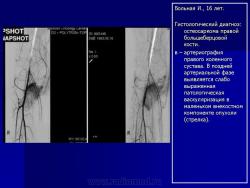

Телеангиэктатическая остеосаркома - редкий (составляет около 4% всех остеосарком) вариант остеосаркомы, характеризующийся наличием кист, заполненных кровью. При рентгенологическом исследовании обычно выявляется полностью литическое поражение без признаков склерозирования, интенсивное вздутие кортикальной пластинки и ее деструкция, часто обнаруживаются периостальная реакция и распространение патологического процесса в мягкие ткани. Гистологическая диагностика телеангиэктатического варианта остеосаркомы может быть относительно несложной при наличии атипичного остеогенеза и высокой степени анаплазии клеточных элементов. Однако довольно часто, особенно у детей и подростков, диагностика вызывает значительные трудности, так как эта остеосаркома, в основном, представлена высокодифференцированным вариантом. Последний отличается тем, что опухолевые клетки определяются только в области выстилки кист и полостей опухоли, злокачественные клетки характеризуются низкой степенью анаплазии, опухолевый остеоид обнаруживается лишь при целенаправленном исследовании серийных срезов, встречаются участки ткани, в которых клеточные элементы и остеоид не имеют признаков атипизма и микроскопическая картина полностью соответствует аневризмальной кисте кости, в связи с чем не исключена диагностическая ошибка при исследовании небольшого количества материала, особенно биопсийного. Относительно медленное развитие опухоли, обычно чисто литическое поражение кости, сходство рентгенологической картины с аневризмальной кистой или гигантоклеточной опухолью кости также способствуют постановке неверного диагноза.